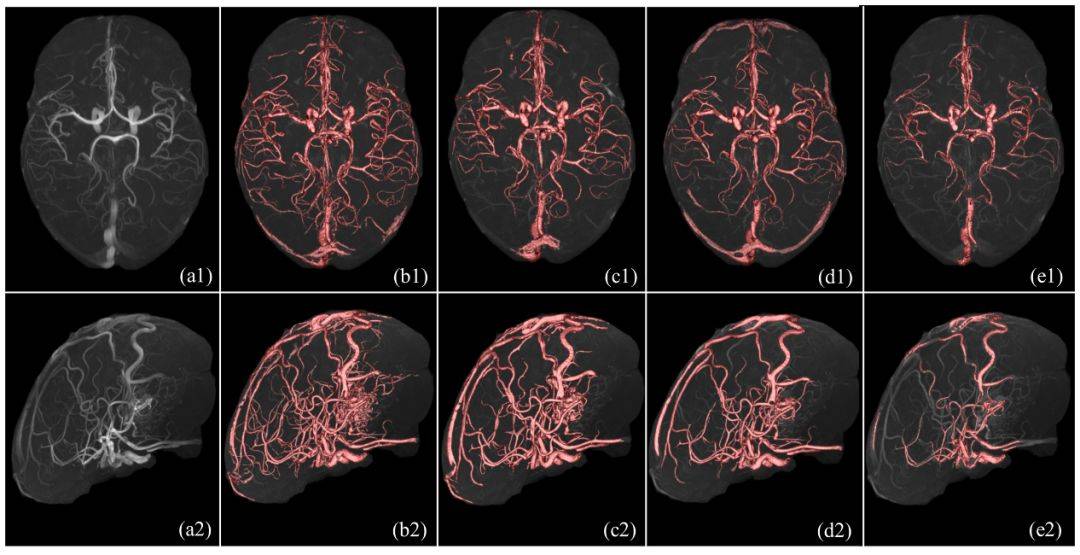

现有的各类脑磁共振血管分割方法依赖于特定MR成像设备或特定数据集,基于模型驱动的血管分割方法通常不能完整地提取脑血管网络并且存在过分割现象,基于深度学习的方法受限于海量数据标注问题。上述两篇论文分别提出了两种鲁棒的统计学方法,实现任意磁共振设备型号下的TOF-MRA三维数据的全脑血管拓扑结构精确提取(如图1、2、3),该研究可以对深度学习方法提供血管数据的自动标注工具;在特定磁共振设备下,实现基于三维TOF-MRA和MR-T1数据的完整脑动脉和脑静脉结构的精确分割(如图4(f))。上述成果对于脑血管的自动标注、分割、临床可视化具有重要现实意义。

图3. 实验结果(一种新颖的设备无关的TOF-MRA数据分割的统计学建模方法)

图4. 由左至右为十套脑磁共振血管造影数据的分割结果:(a)原始TOF-MRA造影数据的最大密度投影视图;(b-e):4种对比方法;(f):本文所提方法;(g-h):动静脉分离结果